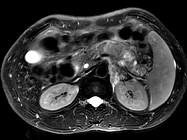

问题 男45岁、腹部胀痛不适、胃纳减退、体重减轻、中腹部可触肿块,影像检查如图,应诊断为()

选项 A.急性胰腺炎 B.慢性胰腺炎 C.胰腺体尾部癌 D.胰岛细胞瘤 E.腹膜后淋巴结结核

答案 C